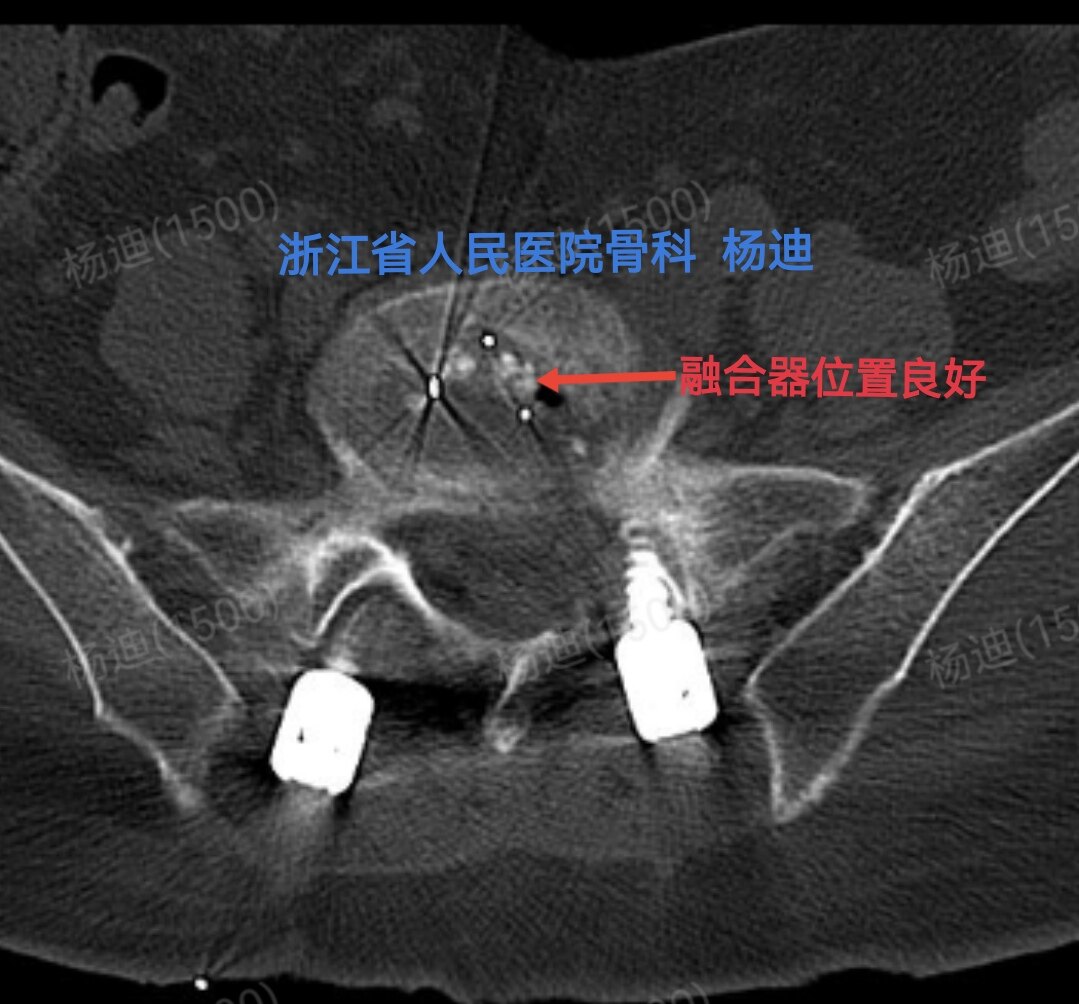

图为术后腰椎CT横断面,提示腰5/骶1间隙融合器位置及长度满意(红色箭头)。

CT冠状位重建:椎间高度恢复(橙直线间距离),融合器位置良好植骨充分(红箭头),螺钉位置良好(黄圈)